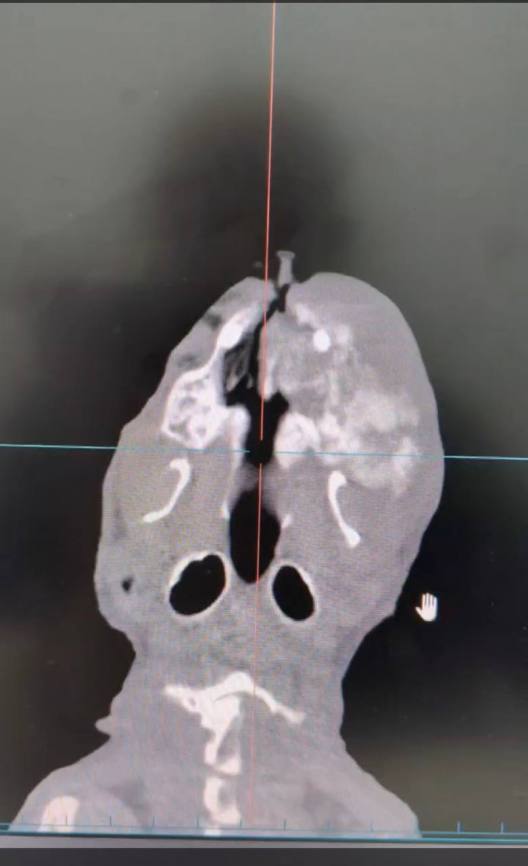

На диагностическое исследование, компьютерной томографии, поступила кошка Дуся, с жалобами на увеличение верхней челюсти. В сторонней клинике предварительной причиной были зубы (периапикальный абсцесс), без должного диагностического обследования. Была проведена экстракция ( удаление) зубов, которая к сожалению не дала положительной динамики. После чего Дуся была направлена к нам на диагностику, в ходе которой было выявлено новообразование, с поражением большого участка костной структуры. С учетом возраста Дуси, ей уже 15 лет, владельцы решили не проводить дальнейшее обследование и лечение, по причине того что операция по удалению данного костного новообразования является очень травматичной. Поэтому всегда важно проводить своевременную диагностику перед постановкой диагноза и назначением той или иной схема лечения.